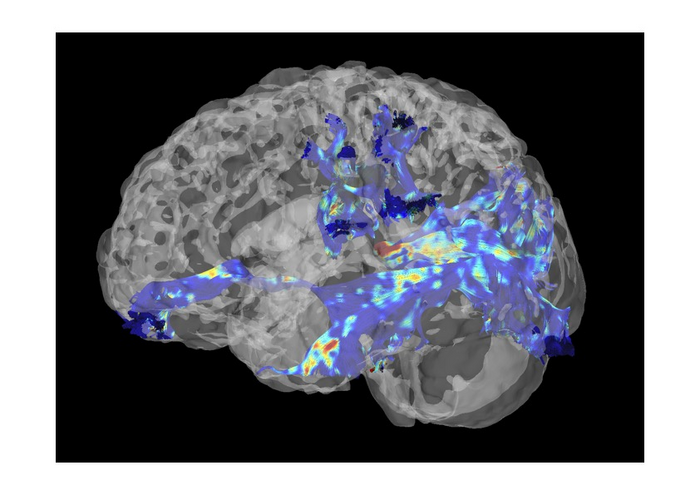

Abu Dhabi, UAE, May 1, 2023: A team of NYU Abu Dhabi researchers, led by Bas Rokers, director of the NYUAD Neuroimaging Center, studied the changes in the brain that can lead to visual skills improvements. The investigators teamed up with Project Prakash, a combined humanitarian and scientific effort to restore sight in curably blind children from rural parts of India. They discovered that improvements in visual functions are linked to changes in white matter pathways, which connect neurons in different brain regions.

They studied many pathways, but only those involved in high-order visual functions, such as face recognition, were directly linked to the visual improvement. Moreover, researchers saw that the patient’s amount of change in late visual pathways, specifically the posterior callosum forceps, predicted the amount of behavioral improvement. This is a new result that identifies the location of brain changes responsible for behavioral improvement.